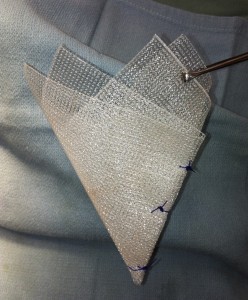

会陰ヘルニア

会陰ヘルニアをポリプロピレンメッシュにより整復

成型したポリプロピレンメッシュ

通常は内閉鎖筋という自己の筋肉を使って整復します。慢性または難治性の場合に限り上記の方法を実施します。